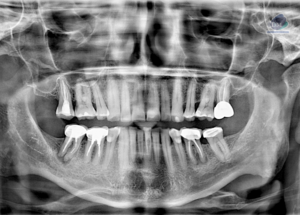

Paciente masculino de 17 años, es referido al Instituto de Diagnóstico Maxilofacial – IDM (Sede Surco) para evaluación del retraso de erupción de la pieza